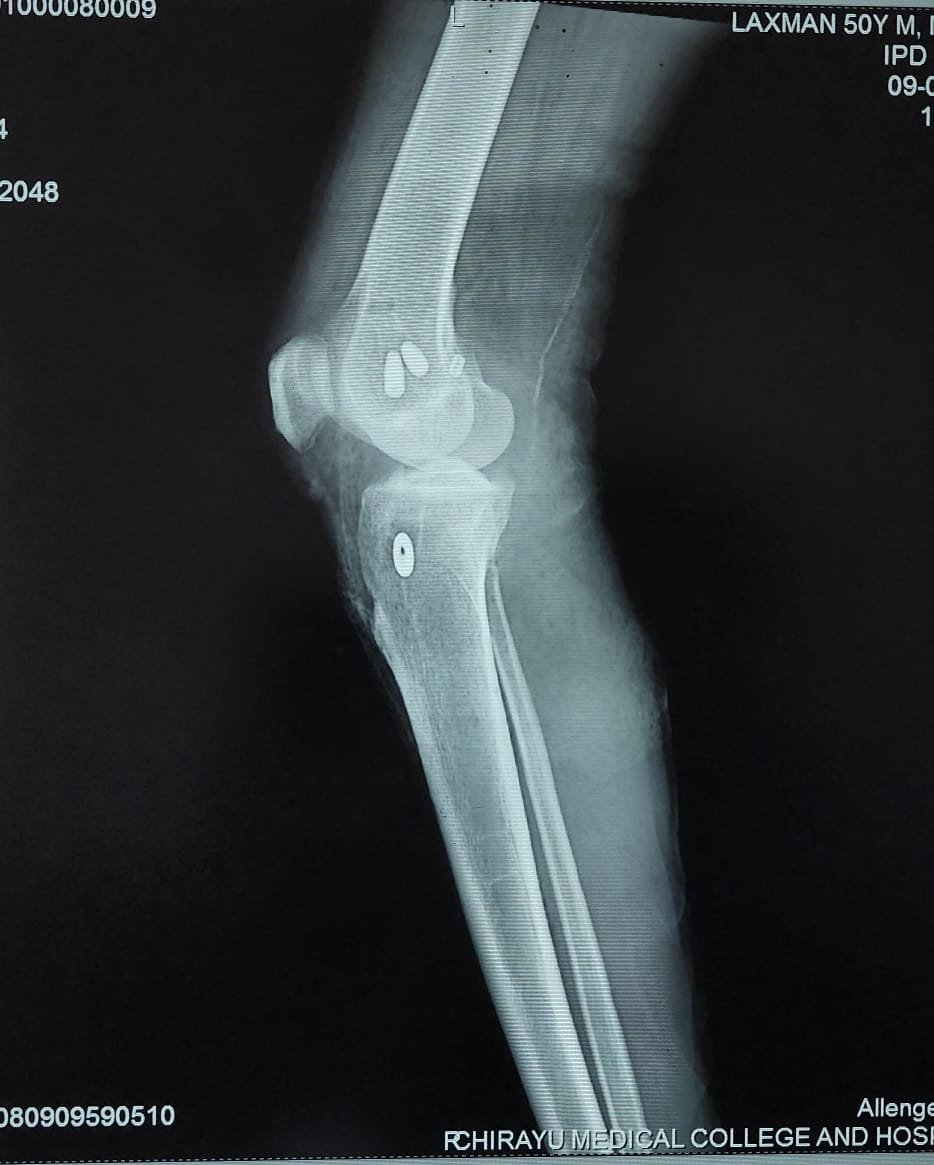

- Fracture Treatment